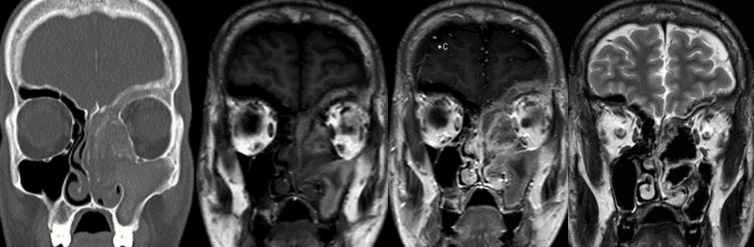

Images of x-rays of skulls

Chronic rhinosinusitis afflicts over 30 million patients in the USA annually, or roughly 12.5% of the population. It has tremendous impacts on the economy and on a patient’s quality of life.  It is defined as symptoms of sinonasal inflammation lasting at least twelve consecutive weeks with corresponding objective physical findings. Symptoms may include nasal obstruction, congestion, nasal drainage, post-nasal drip, facial pressure, loss of smell and/or taste, fever, fatigue, and dental pain. To examine for sinonasal inflammation your physician will use a nasal endoscope to evaluate your nasal cavities and paranasal sinuses. You may also undergo computed tomography (CT) or another form of imaging.

Image of nasal endocopesThere are many causes of chronic rhinosinusitis and the specific cause in any one patient is likely multifactorial. Contributors to the disease process may be environmental, anatomic, congenital, immune, or infectious in nature.